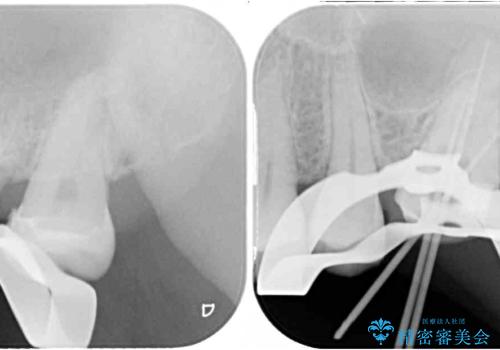

初診時は神経組織の生活反応が認められましたが、2日後に処置を行ったときには、既に反応はなくなっている状態でした。

神経組織は壊死が始まっておりましたが、初回処置後には痛みを感じることもなくなり、2回目に無事に根管治療を終えることができました。